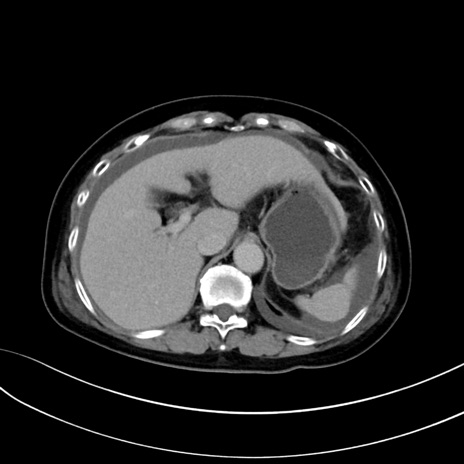

症例13 CT(横断像)1日半後